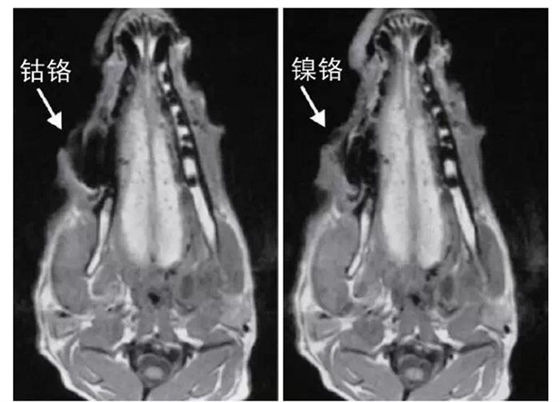

文獻研究中常使用的金屬包括鎳鉻合金、鈷鉻合金、低鈦合金、純鈦、金合金、金鈀合金、銀鈀合金等成分如表所示。大量研究得出近乎一致性的結論。金合金、金鈀合金、銀鈀合金對MRI影響甚微,與全瓷材料、丙烯酸樹脂極為相似,表現為修復體影像邊緣光滑、無變形、無偽影;純鈦金屬對MRI影響較小,接近于全瓷材料;但有的研究卻發現純鈦在核磁共振場中也產生偽影,但偽影涉及的掃描層數較少;低鈦合金(鈦合金)對MRI影響較大,介于純鈦和鎳鉻合金之間,中度偽影;鎳鉻合金、鈷鉻合金對MRI影響很大,鈷鉻合金更甚;表現為重度偽影、圖像扭曲變形(圖1、圖2)。不難看出,對MRI影響,全瓷材料、樹脂材料<金合金等貴金屬<純鈦<低鈦合金<鎳鉻合金<鈷鉻合金。有研究發現鈷鉻合金橋偽影大小與修復體長軸一致,影響范圍為固定橋近遠中徑2倍,頰舌徑的4倍;相同外形金屬修復體厚度增加,偽影增加。單個金屬樁核偽影可波及到上頜竇、牙槽骨、舌體、舌下腺等組織器官,但對眼底、眼內容物、腦組織和頸椎成像基本無影響。

圖2 4種金屬冠在犬MRI檢查中的影響,圖片引自《實用口腔醫學雜志》2014第30期《4種金屬冠對磁共振成像影響的對比研究》一文,作者高嵐等